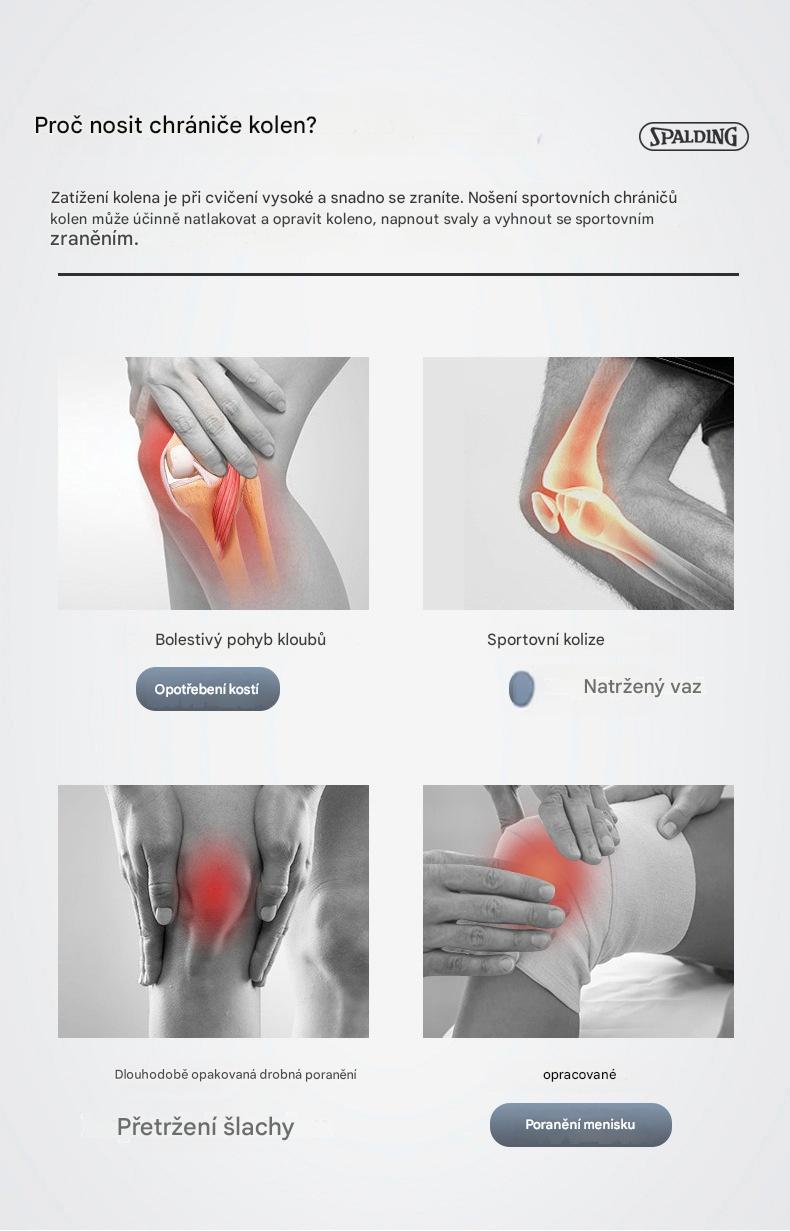

Dostawca: BBKEBAG

Typ: 运动户外>运动护具>运动护膝

Cena:

690.00